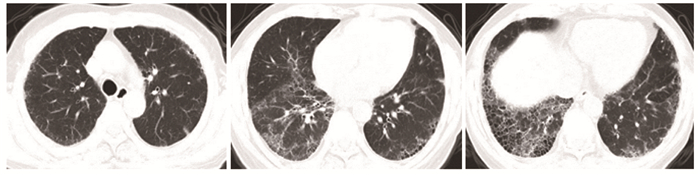

• 摘要: 本文报道一例肺、肾受累的抗中性粒细胞胞浆抗体(antineutrophil cytoplasmic antibodies, ANCA)相关性血管炎患者, 给予经典的糖皮质激素、环磷酰胺、血浆置换诱导缓解治疗有效。该患者在使用硫唑嘌呤维持治疗期间共出现2次感染, 后换用超小剂量(100 mg/次)利妥昔单抗维持治疗病情稳定。个体化利妥昔单抗治疗ANCA相关性血管炎效果显著, 同时避免了过度免疫抑制, 减轻了患者的经济负担。本例患者的诊疗经验有助于提高临床医生在ANCA相关性血管炎维持治疗方面的认识。

Abstract: We reported a case of ANCA-associated vasculitis with pulmonary and renal involvement that was effectively treated with glucocorticoids, cyclophosphamide, and plasma exchange therapy. The patient suffered two infections during maintenance treatment with azathioprine and was later switched to ultralow-dose (100 mg) rituximab to keep the disease in remission. Individualized rituximab therapy is effective in treating ANCA-associated vasculitis, while avoiding excessive immunosuppression, and reducing the financial burden. The diagnosis and treatment of this patient may help clinicians improve their understanding of maintenance therapy for ANCA-associated vasculitis.